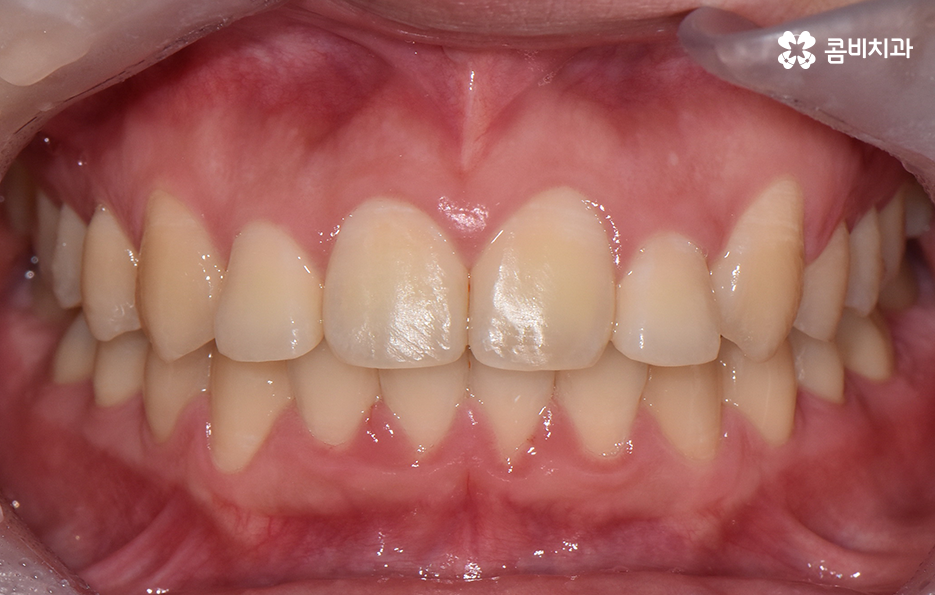

오늘 덧니 비발치 교정 사례로 보시는 환자분의 경우에는 윗니와 아랫니 앞니 부분에 조금씩 덧니가 있는 상태로 덧니를 제외하면 대체적으로 치열 상태는 고른 편이며 덧니 교정 사례 중에서는 돌출입도 함께 개선해야 하는 경우가 많지만 위 환자분의 경우에는 돌출입의 정도가 양호했고 입술라인 역시도 정상 범위에 가까웠기 때문에 발치를 필요로 하지 않았지만 치아의 이동 공간과 보다 자연스러운 입술라인 그리고 얼굴형과의 조화를 고려하여 악궁 확장과 어금니 후방 이동을 적절히 활용하여 교정 치료가 진행되었다고 볼 수 있어요

치아교정 기간은 개인차가 워낙 크기 때문에 교정에 대한 예상 기간을 치과 방문 없이 예측하기란 어렵기 때문에 정확하게 예상하려면 치과에 방문하는 것이 좋겠지만 보편적으로 말씀드리자면 치아가 이동해야 하는 이동량과 정도에 따라서 차이가 커진다고 볼 수 있어요. 예를 들어 발치교정에 비해 오늘 소개드린 덧니 비발치 교정이 치아의 이동이 필요한 정도가 적기 때문에 치료 기간 역시도 비교적 짧은 편이라고 할 수 있으며 오늘 소개 드린 케이스의 경우 약 1년 3개월 정도만에 치료가 마무리될 수 있었어요

정리하면 오늘 소개드린 덧니 비발치 교정 사례의 경우 기본적으로 덧니의 정도나 전체 치열의 상태가 대체적으로 양호한 편이기도 했지만 얼굴형이나 골격적인 부분, 입술라인으로 볼 때도 덧니 교정 사례에서 자주 보이는 돌출입의 개선에 대한 니즈가 큰 편은 아니었기 때문에 비발치 교정으로 충분히 치료가 가능했고 발치를 해서도 안되는 케이스에 속했어요. 아무래도 덧니 교정하면 발치 교정 케이스가 많다보니 겁부터 내시는 분들도 많긴 하지만 덧니 교정 사례도 워낙 다양한 사례가 많기 때문에 자신에게 적합한 치료 계획을 치과 검진을 통해 교정 전문의와 충분히 상의하신 다음에 좋은 판단 내리시길 바라고 있어요